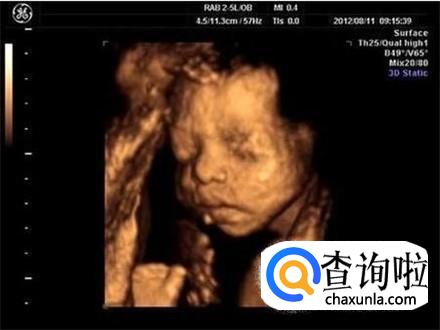

从专业技术的角度上来说,四维彩超是确实能够看到胎儿的性别的,因为和其他的超声波检查项目相比较的话,四维彩超能够实时显示宝宝的动态,从而能够看出性别。

但是,从国家规定的角度上来说的话,国家是禁止给胎儿做相应的性别检查的,因为有的地区确实还存在重男轻女的情况。

为了顺从国家的政策,医生在进行四维彩超检查的过程中,就会对性别特征的部位进行回避,并且后期制作光盘的时候也会进行相关的处理。

所以一般情况数下来说的话,去正规的医院检查的时候,就算做四维,医生也是不会告诉你性别的,除非你找比较熟悉的医生去做。